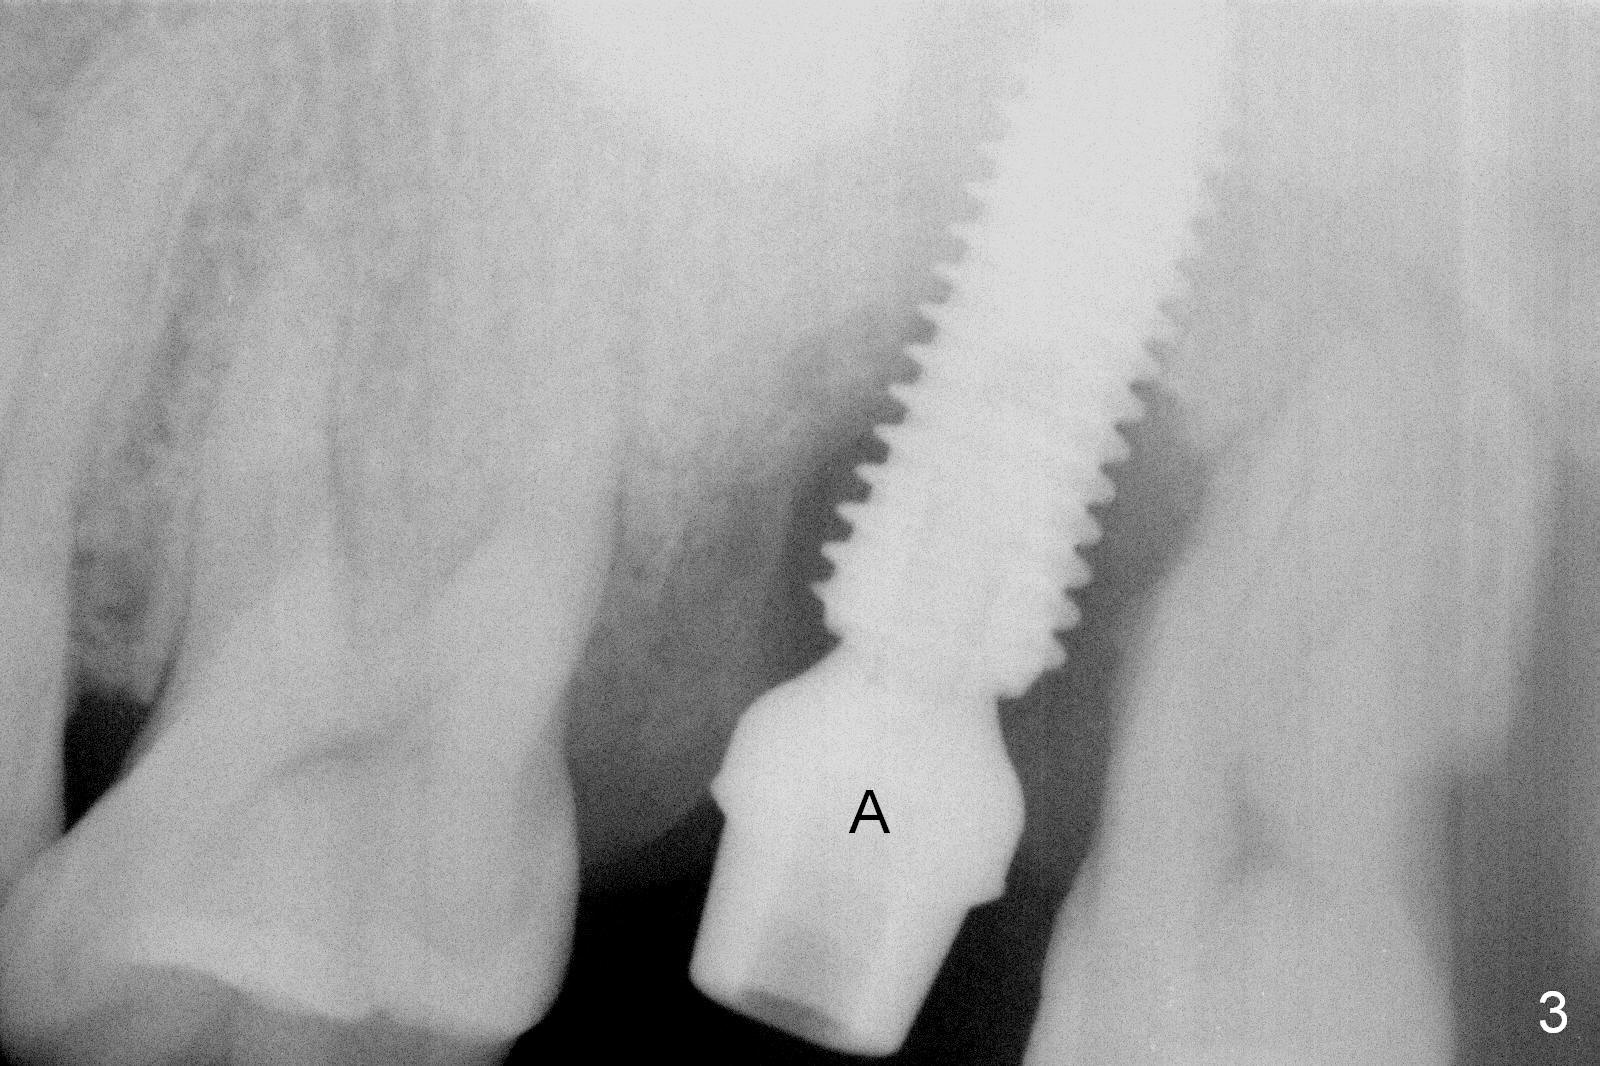

When the tooth #15 is extracted, the buccal plate is found to have been lost. The depth of osteotomy in the native bone is 8.5 mm (Fig.1,2). When a 5.5x15 mm implant is placed (Fig.3), the insertion torque is > 55 Ncm. The implant is palatally placed with a 10x10 mm Osteogen plug being placed in the deep portion of the buccal gap for buccal plate repair (Fig.4 *). The superficial portion of the remaining socket is filled with .5-1.5 mm allograft/autogenous bone/Osteogen (Fig.5 *). The drawback of this procedure is that the abutment is placed prior to placement of the graft. The latter fails to reach the deepest area of the defect. If periimplantitis develops because of insufficient graft, do it again in due time.